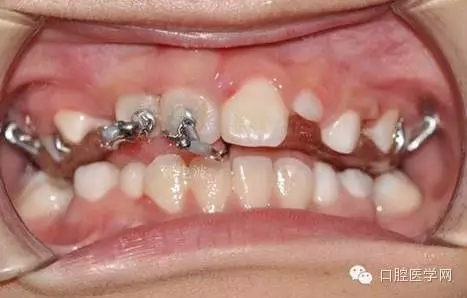

每周復(fù)診:清洗,加力,適當(dāng)調(diào)整吊桿方向

39.webp.jpg

40.webp.jpg

41.webp.jpg

42.webp.jpg

用時(shí)9周完成埋伏牙牽引。

44.webp.jpg

孩子自信的微笑,是我們最大的幸福。